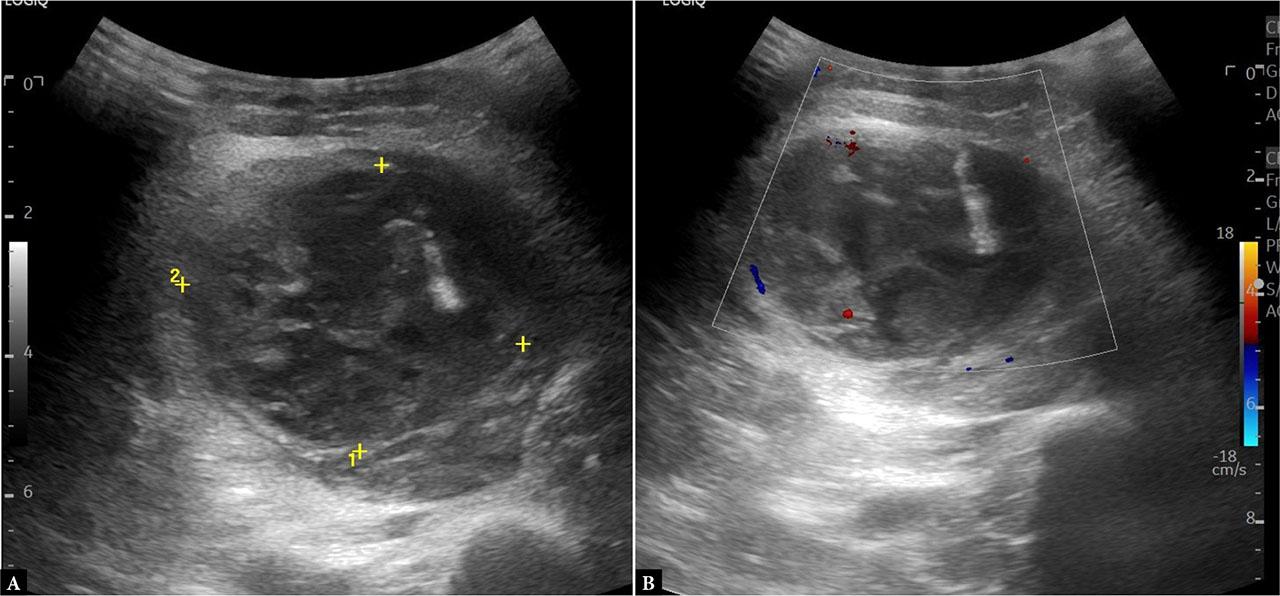

Given the patient’s underlying hematological condition and the localized nature of the symptoms, an urgent US examination of the abdominal wall was performed. The US demonstrated focal thickening and heterogeneity of the left rectus abdominis muscle with multiple small anechoic foci, consistent with an intramuscular hematoma (Fig. 1).

Ultrasound of the left rectus abdominis muscle demonstrating intramuscular thickening (6.8 × 1.6 cm) with heterogeneous hypoechoic areas (A) and no internal flow on CD (B), consistent with an intramuscular hematoma. Comparative imaging (C) confirms asymmetry relative to the contralateral side

Educational tip: Use bilateral comparative scanning to identify asymmetry in muscle thickness and echotexture. The absence of internal color Doppler (CD) signal is a key feature that supports the diagnosis of hematoma rather than neoplasia or abscess.

Clinical correlation: In thalassemia, factors such as iron overload, liver dysfunction, and platelet abnormalities increase bleeding risk. This explains the occurrence of spontaneous hematoma in the absence of trauma or anticoagulant therapy(11,12).